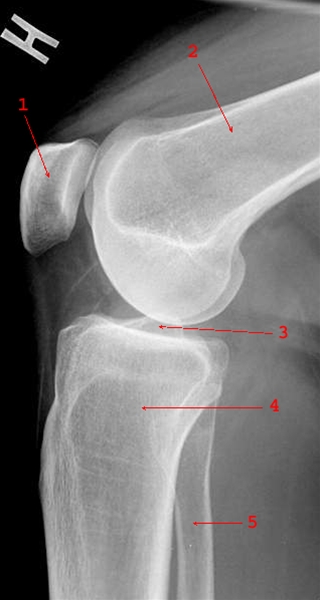

Normalt sidebillede af knæ

1. Patella (knæskal)

2. Femur (lårben)

3. Ledspalte

4. Tibia (skinneben)

5. Fibula (lægben)